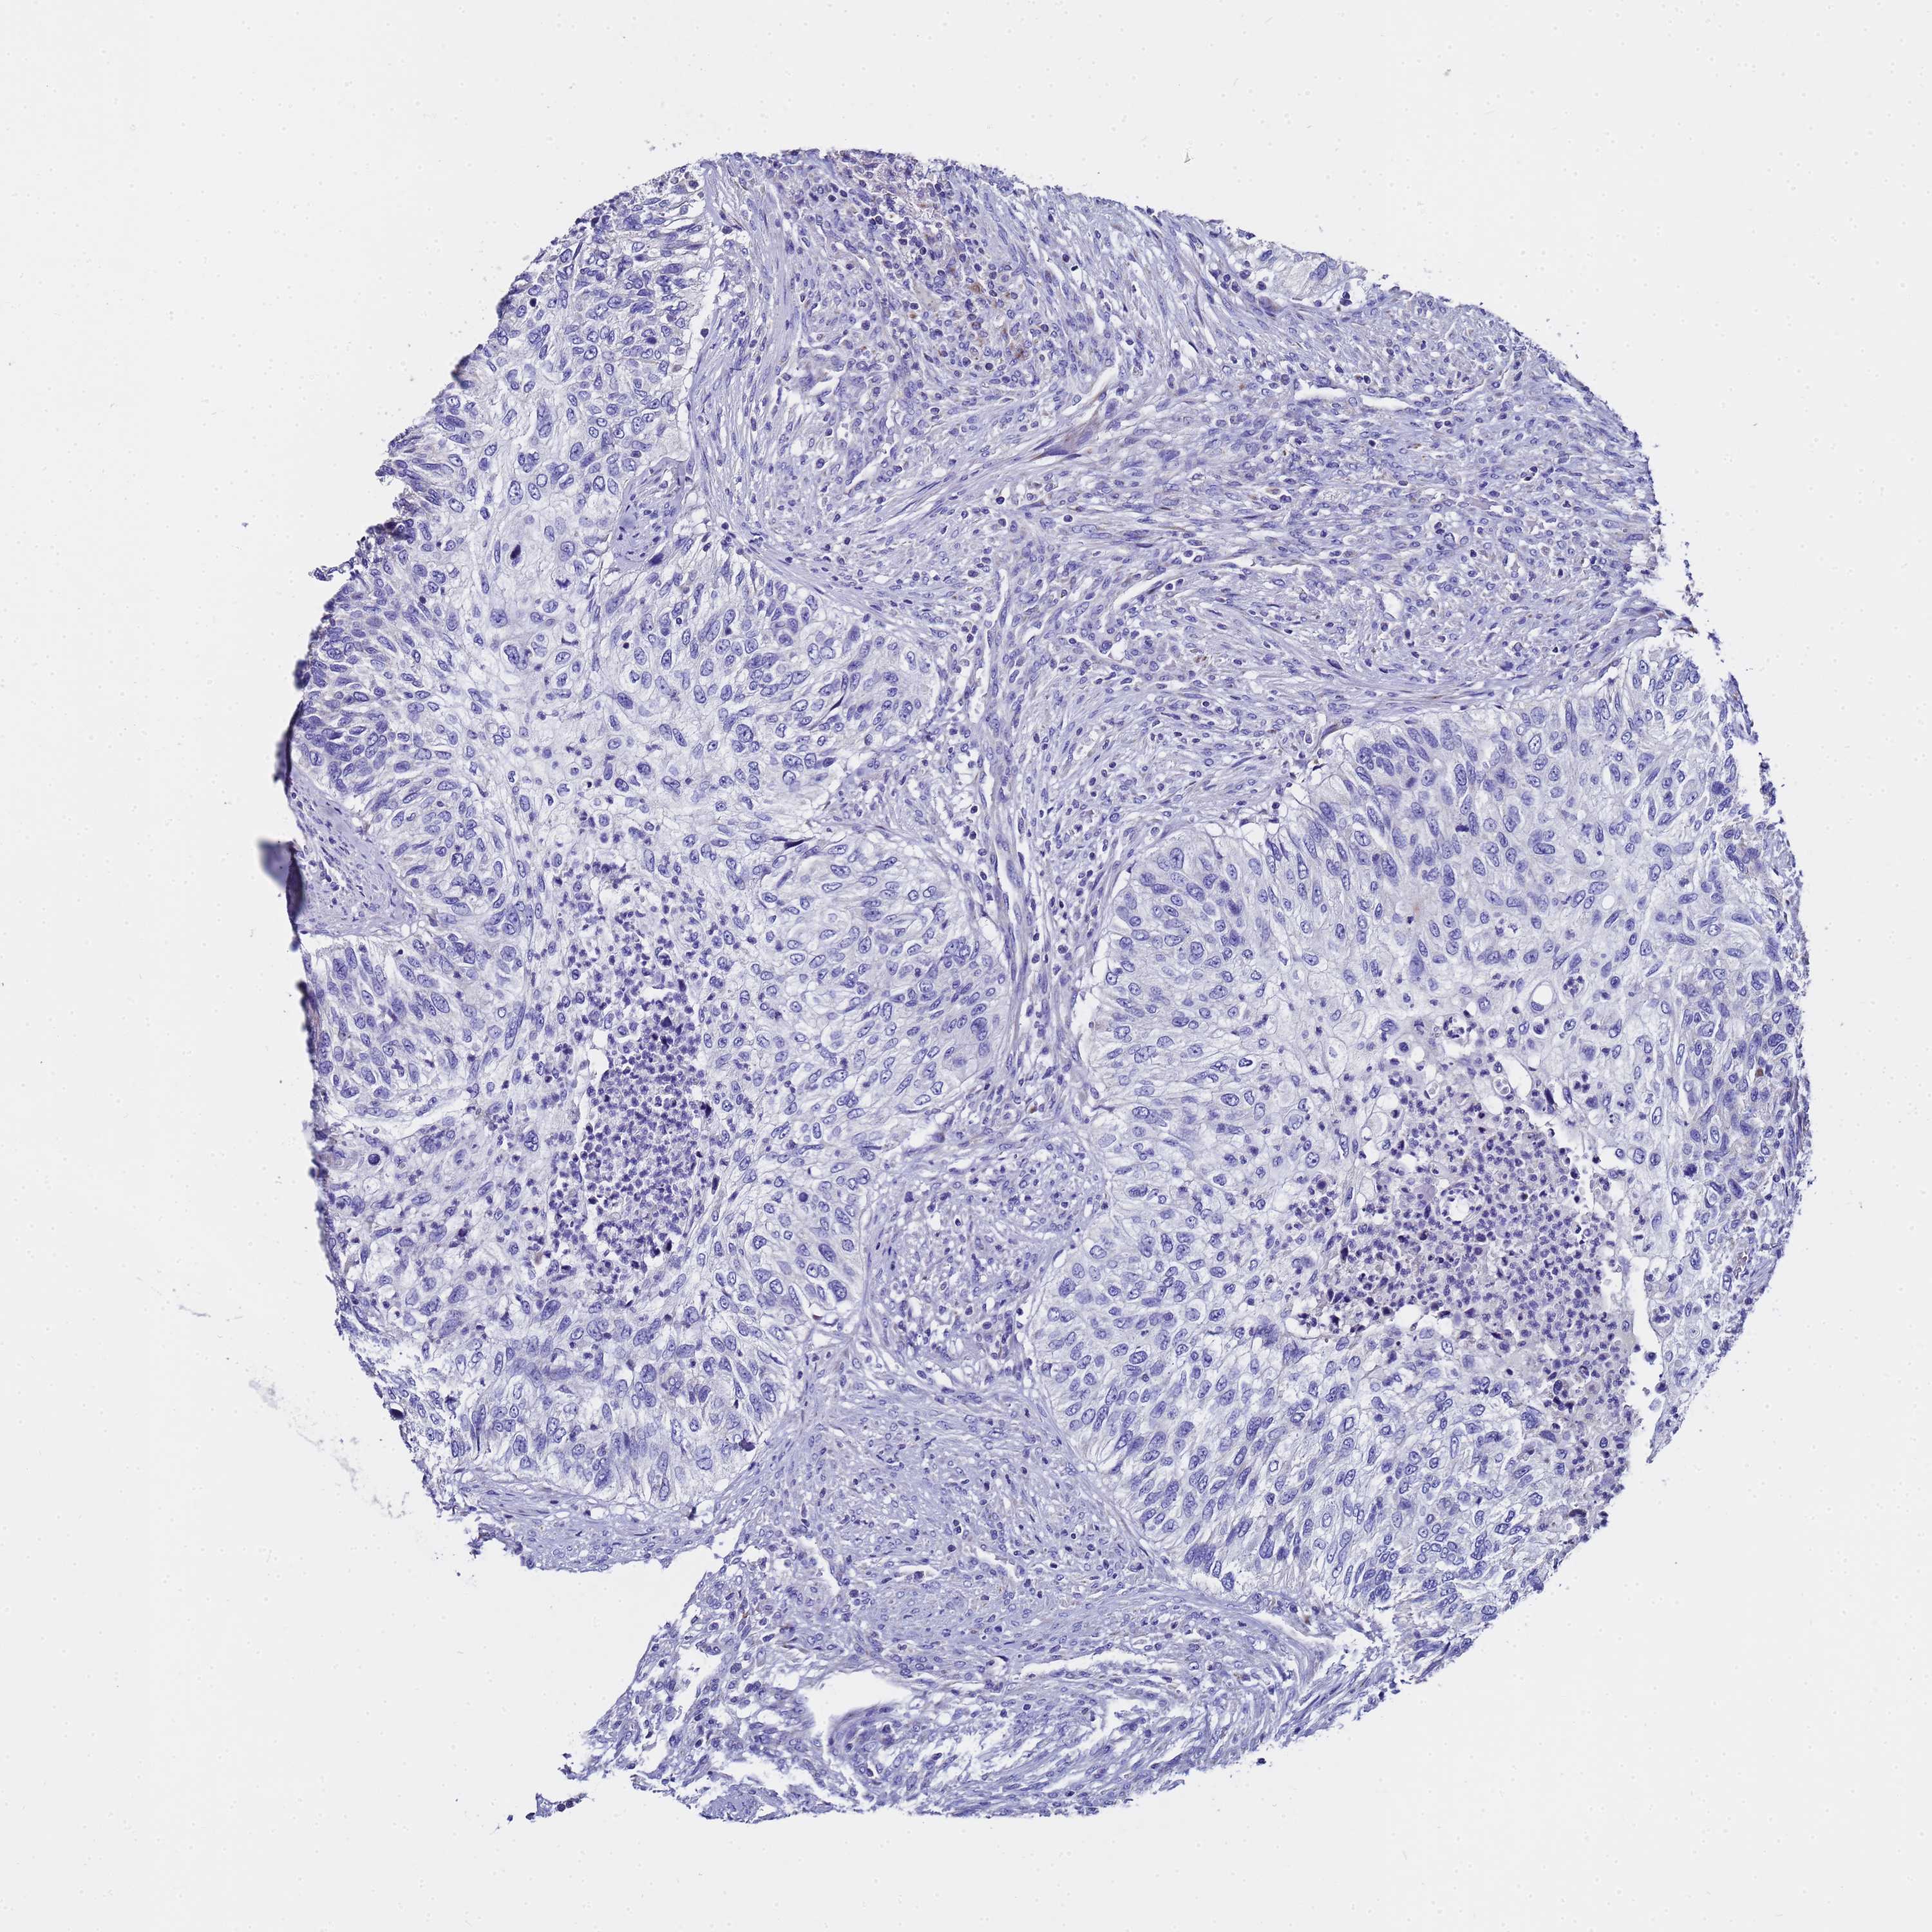

UROTHELIAL CANCER - Protein expressioni

A mouse-over function shows sample information and annotation data. Click on an image to view it in a full screen mode. Samples can be filtered based on level of antibody staining by selecting one or several of the following categories: high, medium, low and not detected. The assay and annotation is described here.

Antibody stainingi

Antibody staining in the annotated cell types in the current human tissue is reported as not detected, low, medium, or high, based on conventional immunohistochemistry profiling in selected tissues. This score is based on the combination of the staining intensity and fraction of stained cells.

Each image is clickable and will lead to virtual microscopy that enables deeper exploration of all samples and also displays staining intensity scores, fraction scores and subcellular localization as well as patient and tissue information for each sample.

Antibody HPA046775

Antibody HPA050633

Staining

High

Medium

Low

Not detected

Intensity

Strong

Moderate

Weak

Negative

Quantity

>75%

75%-25%

<25%

None

Location

Nuclear

Cytoplasmic/membranous

Cytoplasmic/membranous,nuclear

Urothelial carcinoma, Low grade